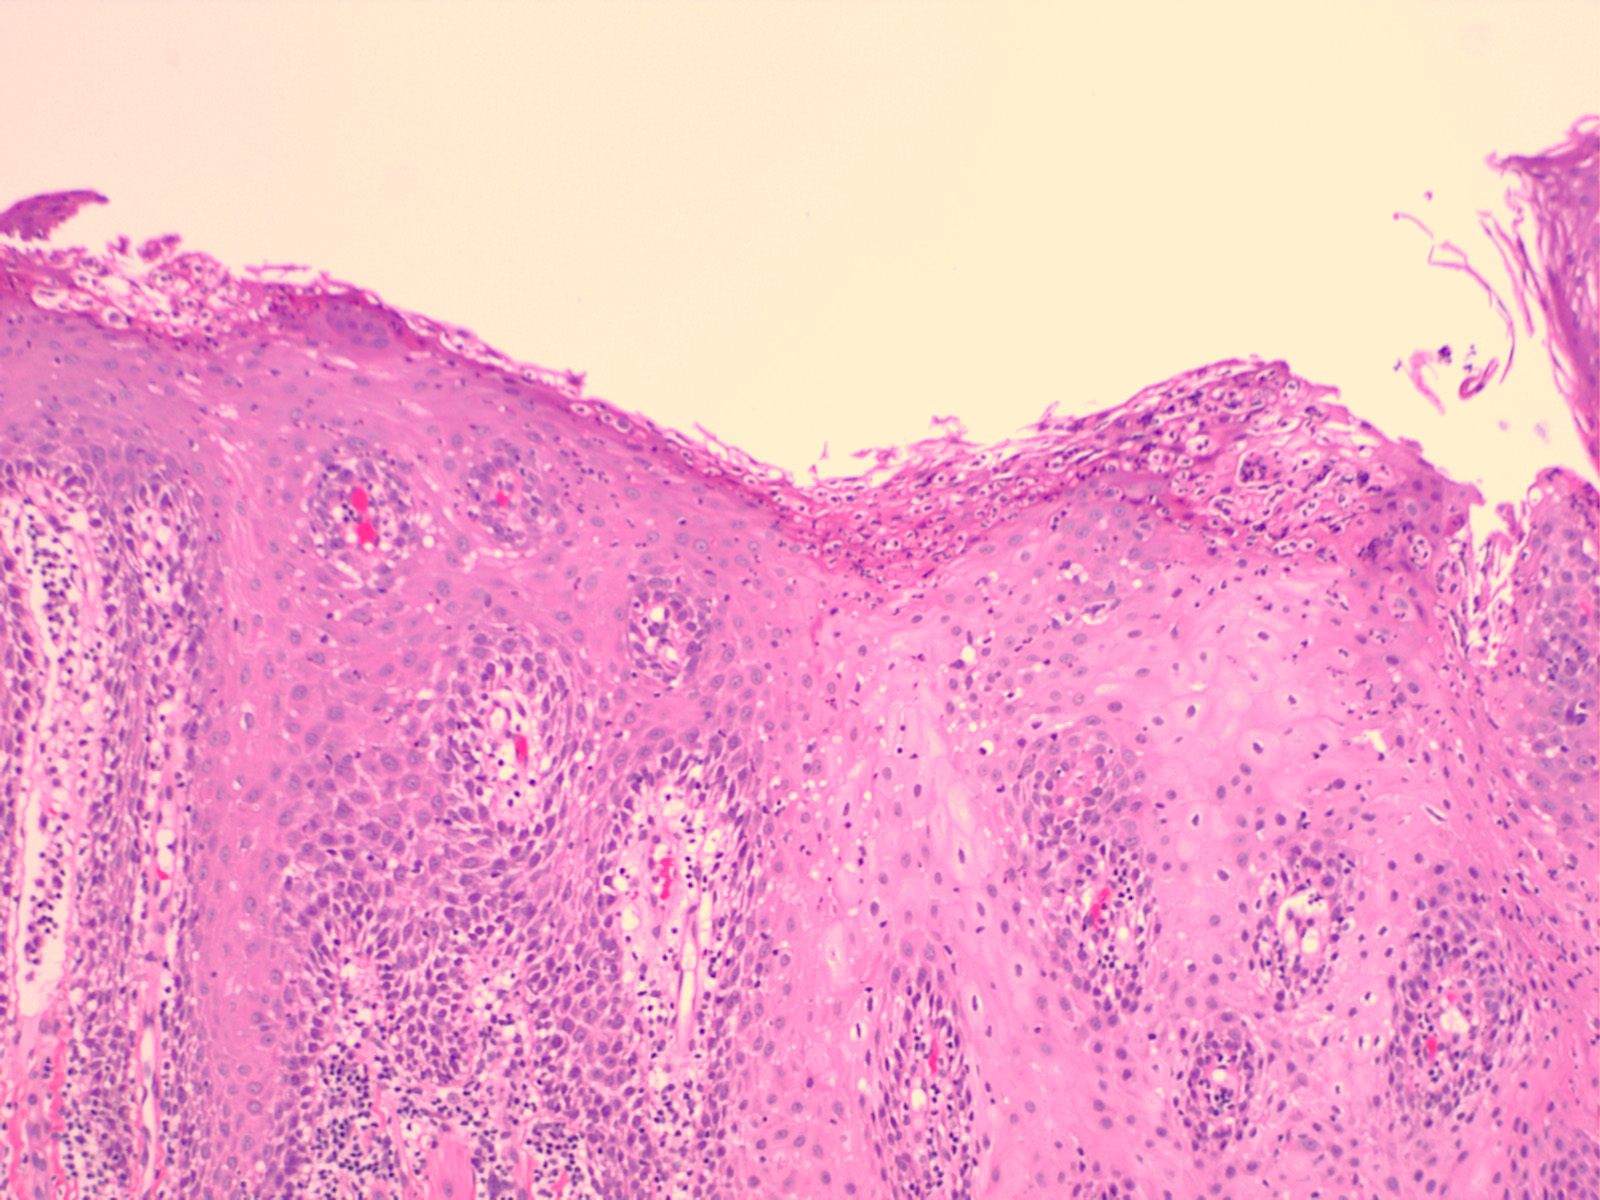

Geographic tongue = اللسان الجغرافي